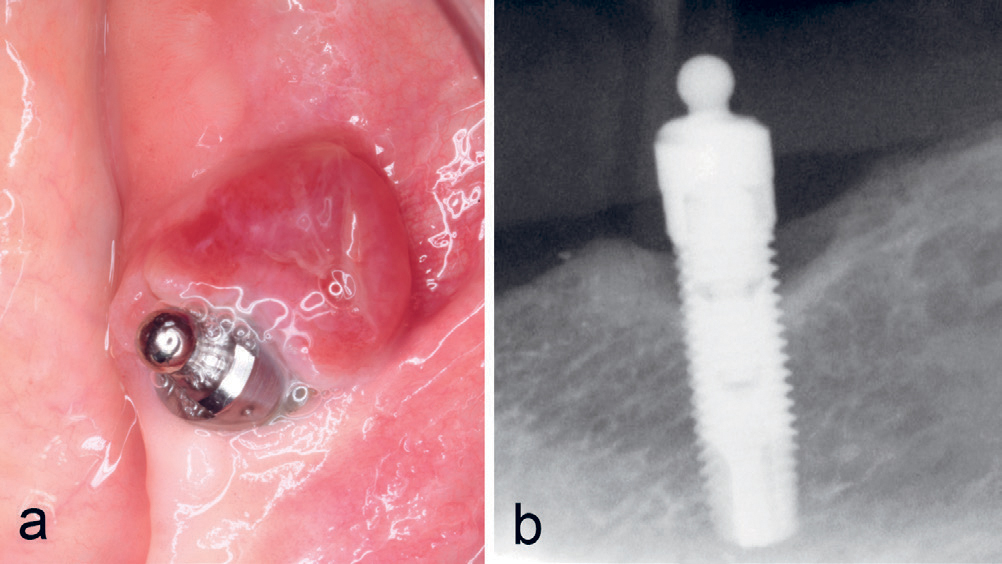

Kasus 15

En 75-årig kvinne var henvist fra tannpleier for vurdering av rød hevelse ved implantat regio 34. Implantatet var innsatt 10–11 år tidligere sammen med et implantat regio 44 som støtte for en protese i en ellers tannløs underkjeve. Det ble funnet en rød hevelse på 7–9 mm distalt for implantatet med kontakt til implantatet (figur 12a) med tendens til peri-implantitt (figur 12b), noe som ble synlig ved biopsi. Lesjonen kom ut i flere biter på grunn av fast tilhefting til implantatet. Diagnosen PKCG ble bekreftet histologisk.

Figur 12. Kasus 15. PKCG distalt ved implantat regio 34 (a) med antydning til peri-implantitt (b).